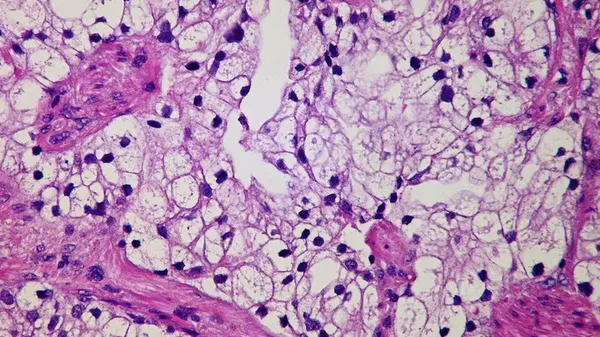

Ultra fine particulate matter (PM), especially fine particles that are 2.5 micrometres or smaller, the so-called PM2.5, may trigger some forms of lung cancer, according to a survey of over 30,000 people in four countries and followed up by further …